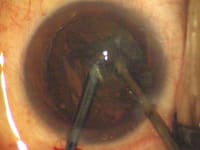

- Dr. Hoffman recommends placing the phaco needle in the eye before the irrigating instrument. He finds that makes insertion easier because there is no fluid pressure working to close the phaco-needle incision. Dr. Olson does the opposite. (See the images on pages 50 and 51.)

Bimanual Microincision Phaco: Key Steps |